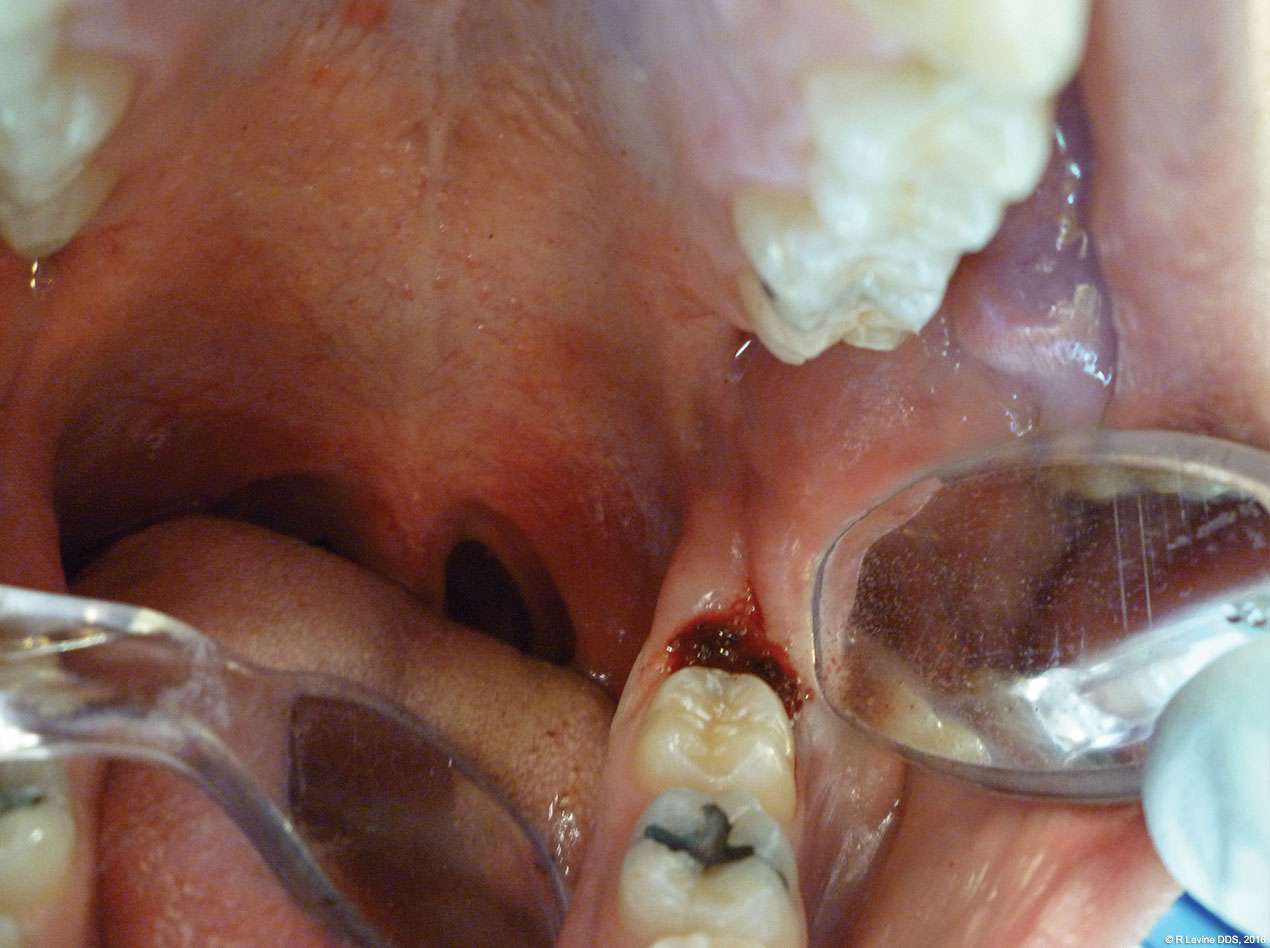

The patient presented with a raised, inflamed, painful operculum distal to the left mandibular second molar (Figure 3). The lesion was red, edematous, and bled easily. A periodontal pocket on the distal of the second molar was > 6 mm deep. There was no evidence of abscess.

- After the initial pass with the laser, the inflamed gingiva bled slightly and the surgeon defocused the beam by increasing the nozzle-to-tissue distance to quickly obtain hemostasis (Figure 6). Note the excellent visualization and the clear operatory field.